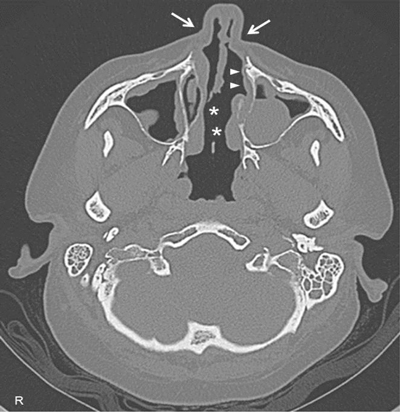

A 45-year-old female came to our attention with a six-month history of ulcerative mass in her right breast. Definitive pathology on breast lesion (Figure 1) documented the presence of a granulomatous mastitis with necrotic foci (asterisk), giant multinucleated cells (circles), and normal breast ducts in transversal (arrow) and longitudinal section (arrowheads) trapped by neutrophilic-eosinophilic infiltrate. Pathologist found no signs of malignant lesions. During the following months, the patient developed worsening cough, shortness of breath, nasal obstruction with hematic discharge, and hearing loss. Chest computed tomography (Figure 2) showed marked wall thickening of the right main bronchus (asterisk), stenosis of the left main bronchus (black arrowheads), and segmental atelectasis in the upper lobe of the left lung (white arrowheads). Paranasal sinuses computed tomography (Figure 3) showed a perforation of the nasal septum (asterisks), absence of the anterior half of the left inferior turbinate (white arrows), and atrophy of the upper lateral cartilages (white arrowheads). Fiberoptic rhinopharyngoscopyscopy documented the presence of extensive crusting rhinitis. Blood tests revealed high levels of antineutrophilic cytoplasmic antibodies with cytoplasmic pattern (c-ANCA). These findings were consistent with diagnosis of granulomatosis with polyangiitis. The patient was put under oral prednisone 1 mg/kg daily and cyclophosphamide monthly pulse therapy, with progressive improvement of breast and nasal lesions. She has currently reached a clinically stable NYHA Class II and is treated with prednisone 15 mg daily, methotrexate 15 mg weekly, and n-acetilcysteine 600 mg daily. She needs periodic endoscopic dilatations of bronchial stenosis.

Figure 3

High-resolution computed tomography of paranasal sinuses, axial projection, showing a perforation of the nasal septum (asterisks), the absence of the anterior half of the left inferior turbinate (white arrows), and the atrophy of the upper lateral cartilages (white arrowheads).